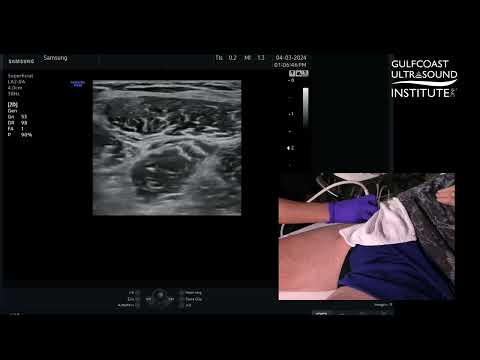

Ultrasound Guided Fascia Iliaca Block

How to Perform an Ultrasound Guided Fascia Iliaca Plane Block

Scanning principles for Infrainguinal vs. Suprainguinal Fascia Iliaca block - NYSORA's Animations